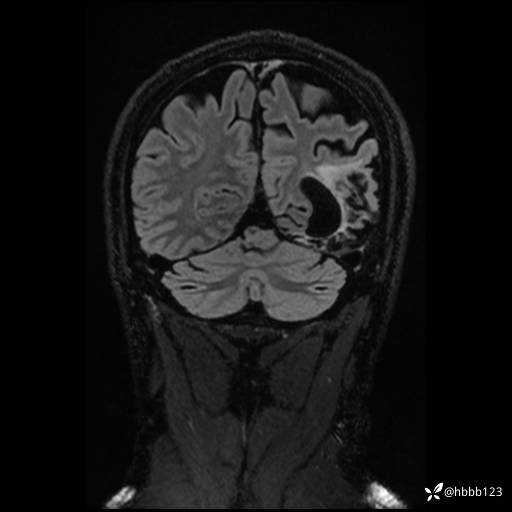

CUBE FLAIR冠状位: